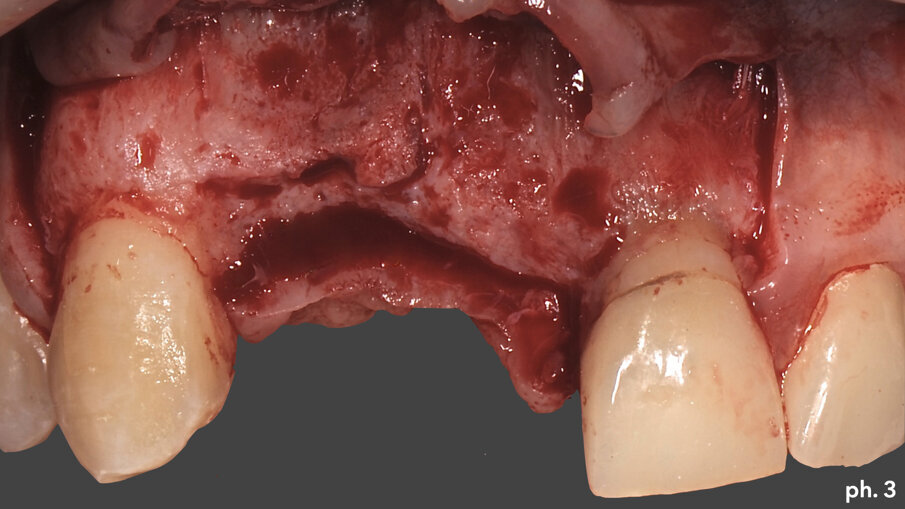

Il paziente, maschio caucasico di 28 anni, si presenta alla nostra osservazione in seguito a un incidente che ha provocato l’avulsione traumatica degli elementi 1.1 e 1.2 con conseguente riduzione dei volumi ossei della zona che, oramai, risulta parzialmente edentula. Sono inoltre presenti in corrispondenza degli elementi 2.1 e 2.2, anch’essi coinvolti nel trauma, due elementi provvisori in resina. La richiesta del paziente è quella di riabilitare la zona edentula con impianti e finalizzazione protesica da 1.2 a 2.2 con corone singole in ceramica1, 2. Dall’esame clinico si evidenzia una carenza di tessuto osseo sia in senso verticale (Fig. 1) che in senso orizzontale (Fig. 2). Si è deciso quindi che l’opzione terapeutica migliore per ottenere una buona rigenerazione ossea di tipo combinato, fosse quella di utilizzare una griglia in titanio customizzata3 in combinazione con un mix di osso bovino deproteinizzato (Geistlich Bio-Oss) e chips ossei prelevati nella zona operata tramite l’utilizzo di un un safe-scraper (Meta)4, il tutto ricoperto da uno strato di matrice Mucograft. Il protocollo operativo delle griglie in titanio customizzate Yxoss CBR prevederebbe l’utilizzo di una membrana in collagene come Geistlich Bio-Gide nella ricopertura della stessa. Personalmente in alcuni casi da me trattati ho deciso di sostituire la membrana in collagene con la matrice, sempre in collagene di origine suina ma in questo caso ricostituito, soprattutto nei settori estetici laddove è richiesta una maggiore quantità di tessuto cheratinizzato al fine di ottenere un risultato estetico migliore. Una volta esposto quindi il tessuto osseo (Figg. 3, 4), si è provveduto ad effettuare una serie di perforazioni a livello della corticale ossea al fine di favorire un regolare sanguinamento (Fig. 5): questo permetterà ai nostri materiali da rigenerazione di usufruire di una maggiore quantità di fattori di crescita, proteine morfogenetiche, ed ottenere quindi una loro migliore integrazione nel tempo.